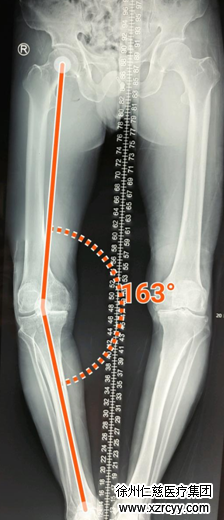

刘师傅手术前照片,双侧膝关节都磨损严重。

刘师傅手术中计算机导航测量的左侧膝关节畸形程度,膝关节内翻16°,屈曲畸形15°。

刘师傅手术中人工关节安装后,计算机导航直接显示人工关节安装的效果,非常理想,完全达到了手术前的预期效果,术后拍片也证实了手术后效果。